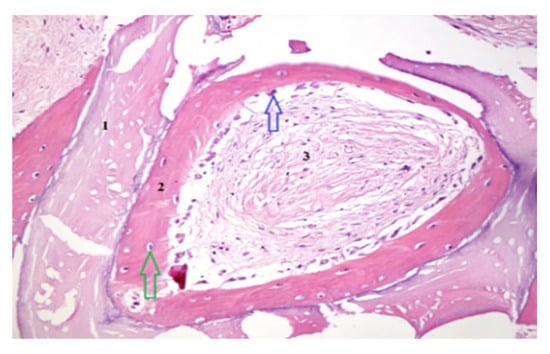

Biopsy specimens were fixed in 10% neutral-buffered formalin, decalcified, embedded in paraffin, and sectioned for Hematoxylin and Eosin (H&E) and Von Gieson (VG) staining. Histomorphometric analysis quantified the percentage of newly formed bone, residual graft particles, and connective tissue using digital microscopy (Zeiss AxioObserver Z1, Viena Austria- Manufactur- Zeiss) and HistoQuest software version 7 (TissueGnostics GmbH, Vienna, Austria). Mechanical properties were assessed by microindentation testing to determine bone hardness and elasticity. For histomorphometric analysis, representative areas of interest—newly formed bone, xenograft particles, and stromal tissue—were carefully outlined at a scale of 400/700 µm. Consistent criteria were applied across the entire patient group to demarcate the boundaries of newly formed bone, xenograft material, and stromal tissue. This ensured reproducibility and accuracy of the measurements for each tissue type (Figure 3 and Figure 4).

3.4. Histological and Histomorphometric Findings

Histological examination revealed active osteogenesis in both SrR and control sites. However, SrR-treated specimens exhibited more mature lamellar bone, denser trabeculae, and reduced residual graft material.

Quantitative histomorphometry showed that SrR-treated samples contained 46–55% newly formed bone, 15–20% residual graft particles, and 25–30% connective tissue, compared with 35–42% new bone, 25–30% graft material, and 30–35% connective tissue in untreated controls.

The results indicate a higher degree of mineralization and bone maturation in the SrR group. Figure 3 and Figure 4 illustrate these histological differences. Scale bars and tissue labels have been standardized to improve figure clarity.

Figure 3. Histological section obtained following RS administration, showing graft particles (1), an osteoblastic reaction (blue arrow) associated with newly formed bone (2) containing osteocytes (green arrow), and regions of stromal tissue (3). Hematoxylin and Eosin staining, magnification 200×.